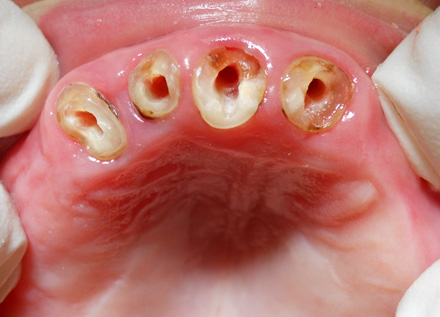

La paziente si presenta alla mia attenzione con scheletrato superiore sostenuto da elementi parodontopatici.Il chief complaint è chiaro:"Non voglio più sentire niente sul palato". Per motivi economici si esclude la soluzione chiurgico-implantare.

Si decide allora per una protesi totale superiore su barra.

Dopo la preventiva bonifica degli elementi irrecuperabili e la devitalizzazione degli unici 4 elementi utilizzabili, si confeziona una protesi totale superiore (senza palato) su barra con 4 ball-attachment a sua volta sorretta dagli elementi naturali precedentemente devitalizzati.